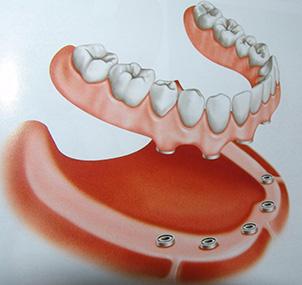

1.Mandíbula sem dentes

2.Instalação de 5 implantes

3.Prótese que vai ser parafusada aos implantes

4.Prótese parafusada em posição

Os implantes possuem algumas etapas que devem ser respeitadas. São elas:

1) CIRÚRGICA onde serão instalados os parafusos dos implantes

2) PROTÉTICA onde serão colocados os dentes fixados nos implantes.

Em alguns casos, previamente ou em conjunto com a etapa cirúrgica pode existir a necessidade de enxertos ósseos (colocação de osso na região que receberá implante).

Antigamente era esperado obrigatoriamente de 4 a 6 meses entre cada etapa para que os pinos de titânio se integrassem ao osso. Hoje sabemos, através de estudos, que a Implantodontia atual permite aos especialistas fazer a reposição, no caso da falta de um ou mais dentes, diminuindo o período de cicatrização e reduzindo custos. Ou seja, pode ser feita a cirurgia em um dia e a colocação da prótese (dentes) no mesmo dia.

Assim sendo, a carga imediata se firma como tratamento viável, desde que a quantidade e qualidade ósseas sejam suficientes, e preferencialmente se aplique o recurso na região anterior de mandíbula (região mentoniana ou “queixo”), onde normalmente se encontra osso mais denso. A carga imediata requer menor número de cirurgias, visto que o sistema tradicional aguardaria um “período de osseointegração” dos implantes, entre 3 a 6 meses. Com o tempo reduzido, maior é o conforto do paciente. Trata-se de uma alternativa de tratamento diante das opções disponíveis para os pacientes sem dentes ou com poucos dentes, cuja situação precária destes não justifique mantê-los.

Prótese antes de ser parafusada nos implantes

Prótese sendo parafusada nos implantes